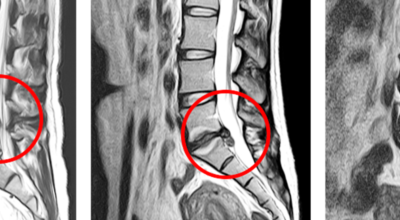

디스크는 그 특수한 구조 때문에 웬만한 힘이 가해져도 효율적으로 쿠션 역할을 할 수 있겠습니다. 그러나 갑작스럽게 무거운 물건을 들어 올리거나, 부자연스러운 자세를 장시간 취하면 디스크에 무리한 힘이 가해지면서 디스크가 밖으로 돌출이 되게 돼요. 심한 경우 디스크를 감싼 막이 터지면서 그 안에 있는 수핵이 튀어나오게 돼요. 디스크는 대부분이 후방이나 후외방으로 돌출되는데 이 경우에 바로 곁에 있는 신경을 누르게 된다고 해요.

돌출된 디스크는 척추의 어느 부위에나 발생할 수 있답니다. 목에 생기면 '목 디스크', 등에 생기면 '등 디스크', 허리에 생기면 '허리 디스크'라고 부른다고 해요. 이와 같이 디스크가 돌출되어 신경을 눌러 요통 및 다리가 아프고 저린 증상을 일으키는 병을 '추간판 탈출증' 또는 '디스크 탈출증'이라고도 불리워요. 발생 빈도별로 보면 허리 디스크가 가장 흔해요. 그다음이 목 디스크입니다. 등 디스크는 드문 병이라고 하네요.